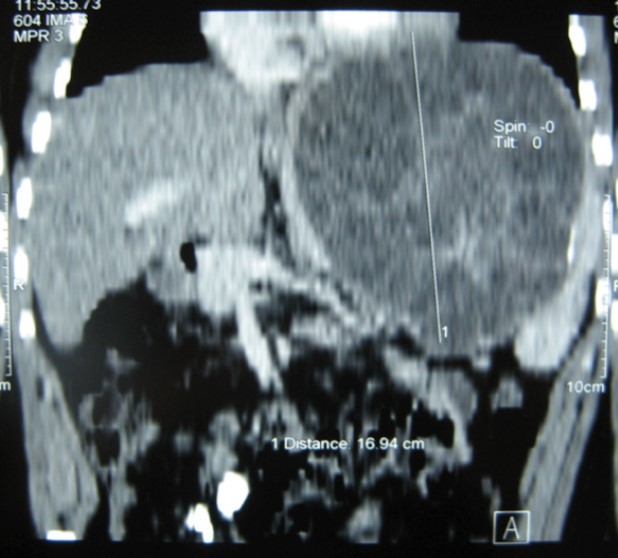

A 17-year-old young man admitted to our department with the complaint of abdominal pain localized in the left upper quadrant for the last 3 months. His physical examination revealed a splenomegaly. Immunoblot assay for Echinococcus was positive. His laboratory tests showed normal results of the serum and urine examinations, No eosinophilia was found. Chest X-ray revealed no pathological signs. An abdominal ultrasonography showed a 20 cm multivesicular cystic mass of spleen (figure 1). Contrast enhanced CT scans detected a huge single 20×16×18cm cystic mass located in the spleen. It had well-defined borders and contained multiple, round, daughter cysts in the periphery of the lesion with calcification (Figure 2, Figure 3, Figure 4). The patient underwent a laparotomy. A large splenic cystic mass was identified, attached to diaphragm, and tail of the pancreas (figure 5). The abdomen was packed with 10% hypertonic saline soaked pads in order to protect peritoneal soilage. A partial cystectomy without splenectomy was performed. Histologic examination of the specimen resection showed an echinococcal organism residing within the hydatid cyst . The patient was discharged after 4 postoperative days. 600 mg per a day of Albendazole therapy was instaured postoperatively and continued for 6 months. Two years after surgery the patient is well with disease free.

Figure 3.CT showing a huge single 20×16×18cm cystic mass located in the spleen

Figure 4.CT showing a huge single 20×16×18cm cystic mass located in the spleen